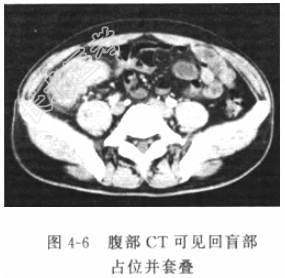

- [材料题] 患者男性,42岁,因“腹胀一周,突发腹痛7h”入院。入院前7天因气温下降受凉后出现“上呼吸道感染(感冒)”,自服“感冒灵”和“阿奇霉素”,服药后自觉“感冒一症状有所好转,但开始出现腹胀伴乏力、不适、食欲下降,稍有恶心,但无呕吐、腹泻和便秘等,上述症状持续约一周。中午在家人劝说下进食了一碗骨头汤,但于下午15时起突然出现严重腹痛,不能忍受,伴恶心、呕吐,经数小时不仅耒见腹痛减轻,反而感到较莆加重,遂于今晚22时急诊我院。本次腹痛发作以来解过一次小便,量不多,呈色黄,无肛门排便及排气。既往有“慢性结肠炎”病史多年,否认其他疾病或手术史。体格检查体温(T)37.8℃,呼吸(R)22次/分,脉搏(P)82次/分,血压(BP)145/85mmHg。神志清楚,查体合作,发育正常,营养中等。皮肤、巩膜无黄染。未扪及浅表淋巴结肿大。颈无抵抗,气管居中,胸廓无畸形,两侧对称,双肺未闻及干、湿啰音,胸膜摩擦音(-)。心律整齐,心浊音界不大,各瓣膜区未听到杂音和心包摩擦音。脊柱、四肢基本正常,未引出病理反射。腹部视诊腹式呼吸消失,腹壁轻度膨隆,未见明显胃肠型及蠕动波。肠鸣音消失,肝浊音界缩小。右侧腹部压痛反跳痛明显,肌紧张。直肠指检未及明显占位,退出时指套无染血。辅助检查血常规示白细胞(WBC)12.8×10⁹/L,中性粒细胞81%,其他实验室检验结果包括肝肾功能、电解质、血气分析结果未见明显异常。腹部立卧位X线平片(图4-5):右膈下见条状透亮区,右膈运动稍弱。腹部CT(图4-6)见小肠管扩张,小肠气液平,可见回盲部占位并套叠。